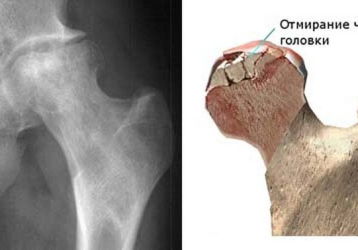

Асептический некроз головки бедренной кости: причины, симптомы, лечение

Асептический некроз головки бедренной кости: причины появления болезни, характерные симптомы, диагностика. Лечение некроза тазобедренного сустава.